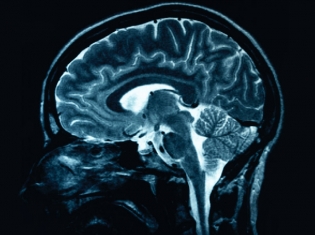

At the same time, researchers were discovering decreases in brain volume in people with bipolar disorder. Studies were showing reductions in the size of brain regions associated with mood regulation.

In an effort to build upon these discoveries, researchers from around the world pooled together their brain imaging data from adults with bipolar disorder.

With this data, the researchers conducted a mega-analysis to examine the differences in brain structure between people with bipolar disorder and people without bipolar disorder.

Their findings show that bipolar patients had increased volumes in the right lateral ventricular, left temporal lobe, and right putamen parts of the brain.

Compared to healthy individuals, those with bipolar disorder who were not taking lithium exhibited a decrease in cerebral and hippocampal volumes.

The key finding of this study, however, was that bipolar patients who were taking lithium showed substantially increased volumes of the hippocampus and amygdala, compared to healthy individuals and bipolar patients not taking lithium.